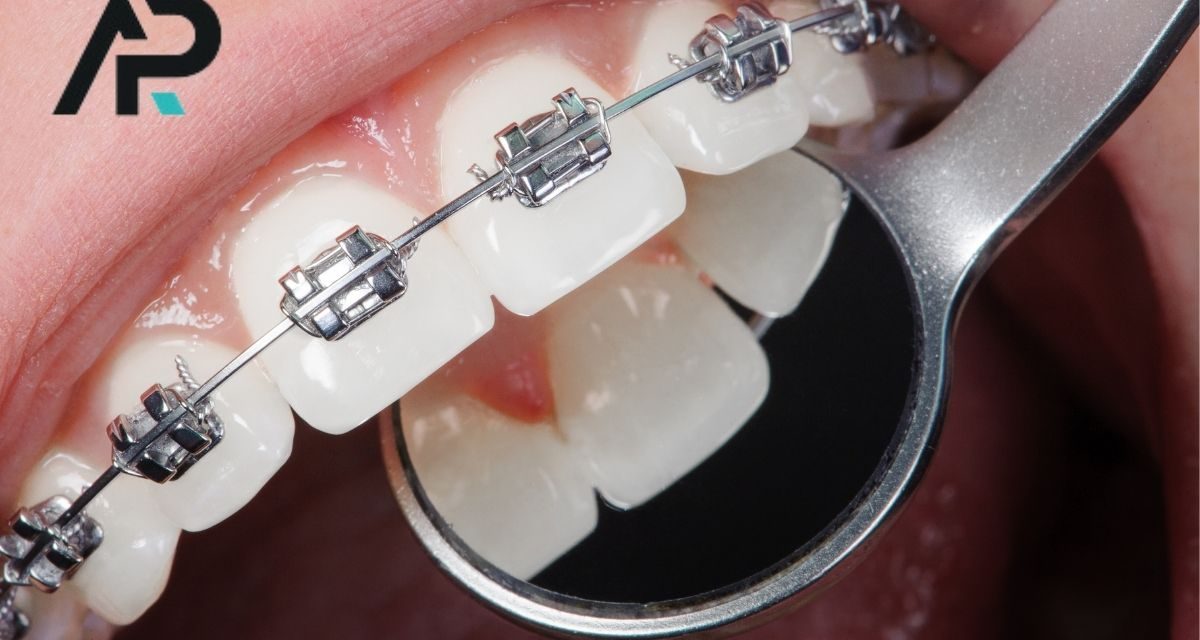

DentAP Grup Ağız ve Diş Sağlığı Polikliniği, Malatya çene cerrahisi alanında uzman hekim kadrosu ve modern tıbbi altyapısıyla hizmet vermektedir. Çene cerrahisi Malatya bölgesinde sadece estetik amaçlarla değil, aynı zamanda fonksiyonel sorunların giderilmesinde de büyük önem taşır. Kliniğimizde gerçekleştirilen işlemler; diş, çene, yüz ve ağız bölgesinde gelişen her türlü sorunun tanı ve cerrahi tedavisini kapsar....